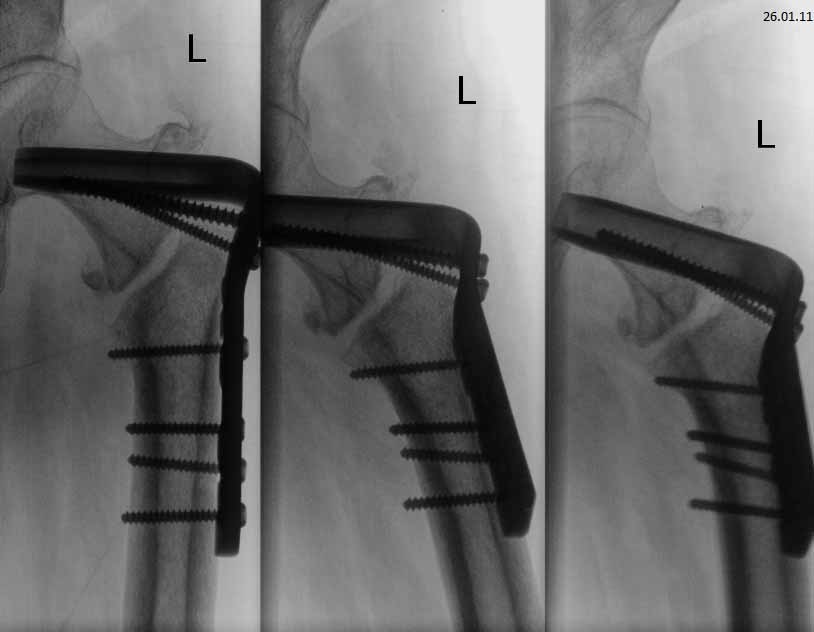

Чрезвертельный перелом левого бедра, в результате ДТП. Женщина 56 лет, ДТП. Чрезвертельный перелом. Было выполнено: скелетное вытяжение- 1 месяц, остеосинтез Г- образной пластиной (Россия), через 4 месяца второй остеосинтез, через 4 месяца вылез винт, выполнена операция- удален один винт, аллопластика. Наложена кокситная повязка. Через 2,5 месяца: щель перелома прослеживается на всем протяжении, склероз по краям отломков. Болей нет. Посоветуйте, что делать дальше, к кому и куда обратиться за помощью. Проживаю в СПб.

Сейчас конструкция несостоятельная. Надо в любом случае ее удалять и заменять на другую, чтобы обеспечить немедленную возможность ходьбы с нагрузкой без риска смещения. Времени на лечение уже ушло в несколько раз больше обычного.

У нас в отделении сейчас делается довольно много операций по такого рода поводам. Предпочли бы сделать остеосинтез стержнем. Есть модификации, исключающие миграцию, подобную случившейся. Делать какие-то пластики и вообще широко обнажать кость не видно необходимости. Возможно, будет целесообразно увеличить шеечно-диафизарный угол.